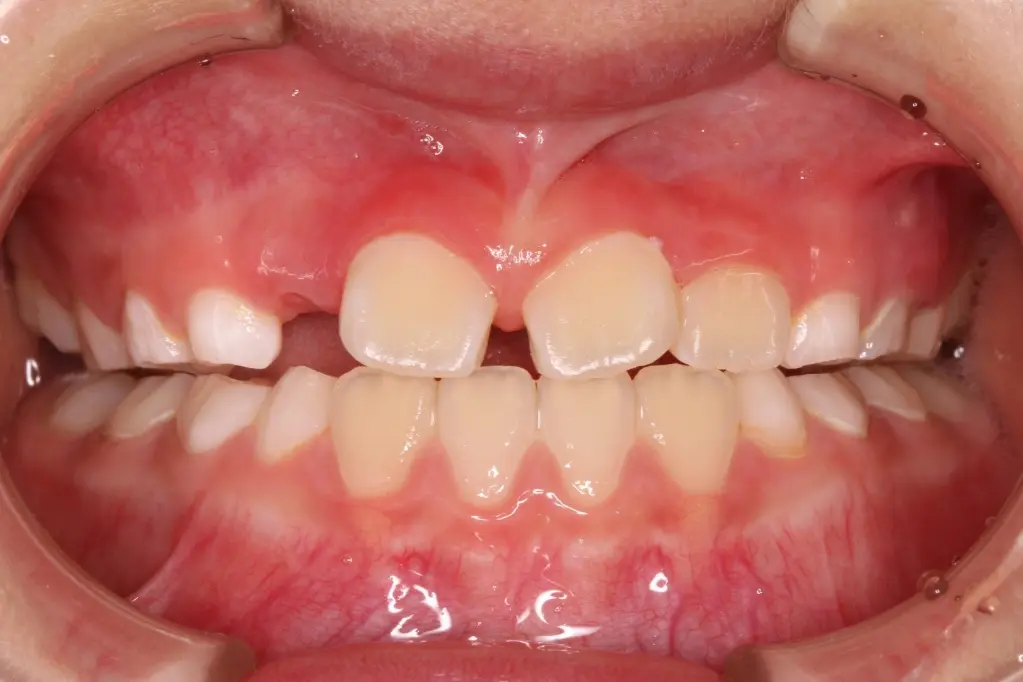

治療開始 8ヶ月後

【反対咬合の改善】

トレーニングと装置の使用により、上の前歯が前に出て反対咬合が改善しました。この後も治療・経過観察を継続していきます。